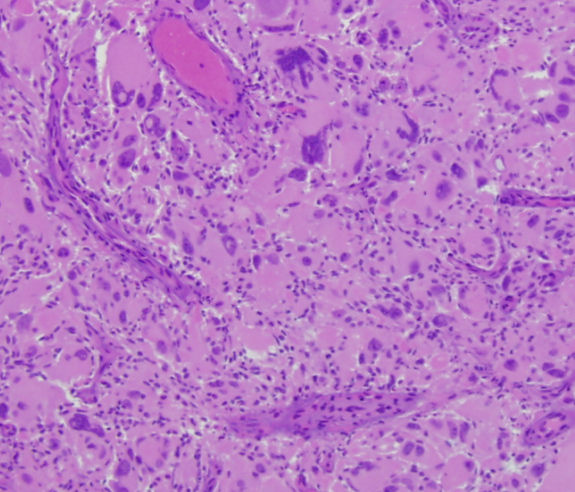

Morphologic Features

• Bizarre, multi-nucleate giant cells with atypical mitotic figures [5]

• Cells may contain numerous nuclei [1]

• Palisading and ischemic necrosis [1]

• Pseudo-rosette like perivascular tumor cell concentration [1]

Hematoxylin and Eosin stained section of giant cell glioblastoma showing bizarre multinucleate cells